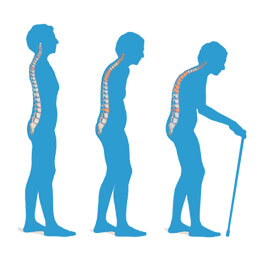

A csontritkulás általában nem okoz semmilyen tünetet. Ellenben sok év után megjelenhetnek az első tünetek, mint: hátfájás, magasság csökkenése, görnyedt tartás. Sok beteg esetében az első tünet egy törött csont, leggyakrabban a csípőben vagy a gerincben. Ha a betegség komolyabbá válik, az ülés, állás, köhögés vagy akár az ölelés is fájdalmas csonttörést okozhat. Kezeletlenül az első törés után még valószínűbb, hogy több csont is el fog törni. A csonttöréses gerincfájdalmat könnyen meg lehet különböztetni a gerincsérv vagy a súlyos gerincferdülés miatti fájdalomtól, mert sokkal erősebb és hirtelenebb, máshoz nem hasonlítható fájdalmat tud okozni. Néhány ember esetében a fájdalom enyhül, ahogy a csont gyógyul, mások esetében tartós fájdalom jelentkezik. A tartós fájdalom kialakulásának esélyét megfelelő csonttörés utáni gyógytorna rehabilitációval minimalizálni lehet. Fontos, hogy fenti panaszok észlelése esetén azonnal forduljunk orvoshoz! A Pharmacoidea Csontok Egészsége terméke a csontok ásványi anyag sűrűségének fokozásával támogatja a csontok egészségének hosszútávú fenntartását, hozzájárulva ezzel a csontritkulás kockázatának csökkentéséhez.

A csontritkulás a gyenge és törékeny csontok állapota. A csontritkulásban szenvedők fő célja a csonttörések megelőzése a csontok erősítésével és az esések elkerülésével. A csontritkulás egy csendes betegség, ami azt jelenti, hogy egyesek nem is veszik észre, amíg el nem törik egy csontjuk. Csontritkulás bárkinél kialakulhat, de az idősebb nőknél gyakoribb. A csontritkulás kockázati tényezői közé tartozik az idős kor, az alacsony testsúly, a dohányzás, bizonyos gyógyszerek (kortikoszteroidok, görcsoldók stb.) és az alacsony csonttömeg (osteopenia). Bizonyos egészségügyi állapotok szintén növelhetik a csontritkulás kialakulásának kockázatát. Ide tartozik az epilepszia, a sclerosis multiplex, a Parkinson-kór, a mellékvese-elégtelenség, a Cushing-szindróma, a gyulladásos bélbetegség, a mielóma multiplex, a sarlósejtes betegség, a HIV és még sok más. A csontritkulás kezelésének egyik legfontosabb célja a törések kockázatának csökkentése az esések megelőzésével, a csontok állapotát javító, rendszeres, de nem megerőltető testmozgással, az alkohol- és a koffeinbevitel korlátozásával, a dohányzás elkerülésével, a napfénynek való kitettség növelésével és a megfelelő kalcium és D-vitamin bevitelt biztosító, egészséges étrenddel.